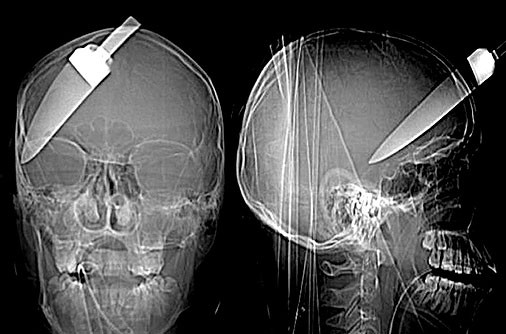

(Poza 2) De o intamplare nefericita a avut parte si un barbat din Bucuresti, care a fost vazut umbland pe strada cu un cutit infipt in cap! Barbatul a fost dus la spital unde a fost operat de medici.

(Poza4)Ajungem in Marea Britanie, unde un barbat a supravietuit unui atac violent. Un cutit de bucatarie i-a fost infipt in cap, la doar cativa milimetri de creier.